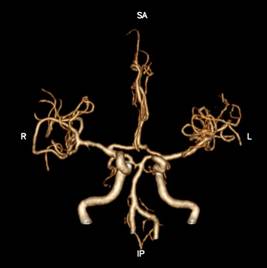

2、脑卒中一站式完成多期扫描

Apex CT通过DLIR技术,突破以往CT需要多次打药、多次扫描的弊端,实现一次对比剂注射下得到CTA、CTV、灌注等临床所需图像,极大缩短抢救患者检查时间。